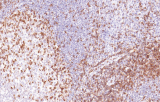

- Assegnazione del lignaggio & principali diagnosi differenziali: Fenotipizzazione cellule B vs cellule T (es. CD20 vs CD3), supportata da fattori di trascrizione nucleari delle cellule B come PAX5 quando i marcatori pan-B sono deboli/assenti.

- LLC/LLS: co-espressione caratteristica di CD5 e CD23 nelle cellule B CD20+ (l'interpretazione richiede consapevolezza del pattern perché sono presenti cellule T reattive).